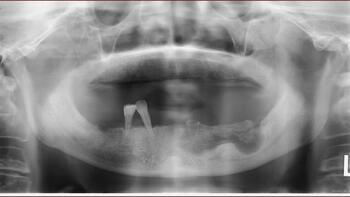

前述した通り、口腔粘膜への顎骨の露出が最大の特徴です。そこに口腔内細菌による感染が伴うと、周囲歯肉の腫脹や排膿、疼痛を伴うようになります。写真1 はデノスマブによるONJ症例ですが、左下顎に広範囲のONJが生じています。歯科用パノラマX線写真を撮影すると写真2 のように写ります。左下顎に広範囲の透過像が認められ、顎骨表面だけでなく内部にも壊死が進展しているのがわかると思います。

写真1:デノスマブによるONJ症例

写真2:歯科用パノラマX線写真